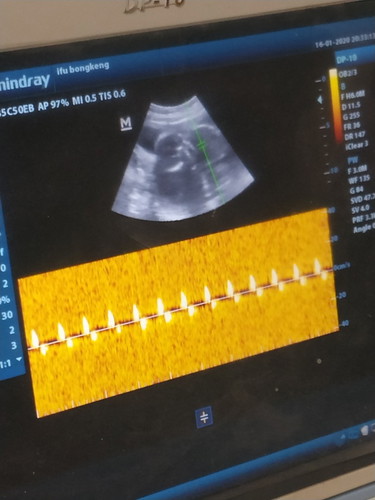

18week

PujiTuhan kata dokternya debay sehat aktif detak jantungnya juga aktif, semoga lancar sampe waktunya dan tidak ada yg kekurangan suatu apapun semuanya sehat amin ?βΊ tapi jk nya belom kliatan ?